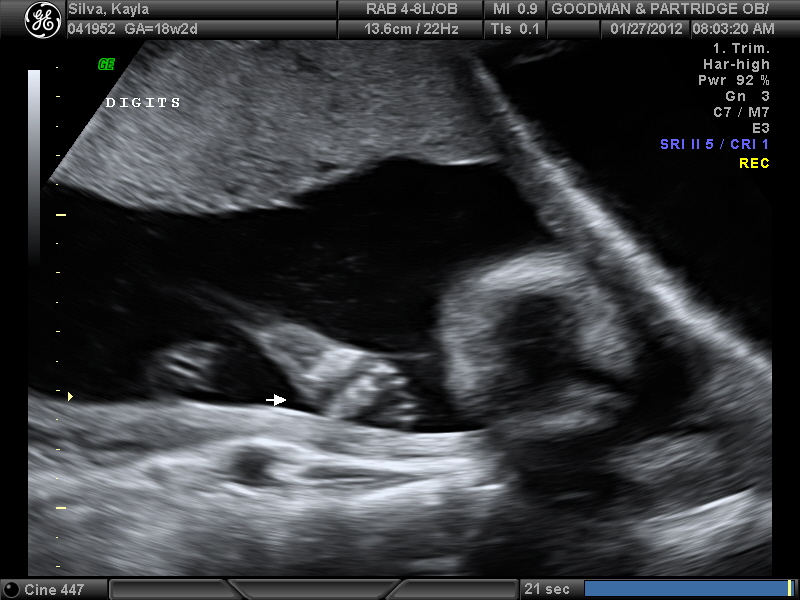

This picture shows my little naughty baby covering its face up. You can see the formation of a hand and fingers. The ultrasound requested that we come back for another ultrasound because they have to count the fingers. The baby was moving its arms around so much we couldn't see the hands for more than a second at a time. Our little creature is a jokester. When ever we got a glimpse of its face, it quickly put its arms over it. It was hilarious. It was as if it knew we were trying to get a look at the face. He was playing peekaboo with us for sure. We were really lucky to have this shot of the fingers! I just wish we got a picture of the face.